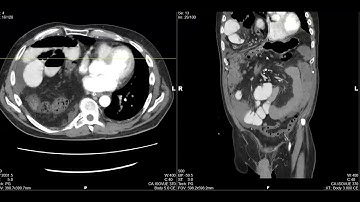

Retrocecal #Hernia with closed loop small bowel #obstruction